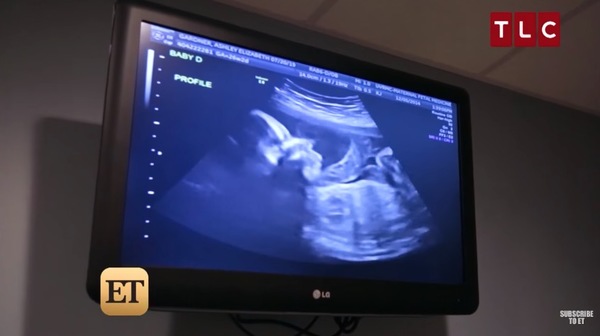

Sonunda o gün geldi çattı ve çift ultrason için doktorun yolunu tuttu. Tyson, müjdeli haberi almak için sabırsızlanıyordu.

Sonunda doktor müjdeli haberi verdi. Ashley hamileydi.

Ancak tek sürpriz bu değildi.

Ashley ve Tyson, ultrasonda bebeklerine ait küçük bir görüntü için dünyaları verebilirdi.

Doktor, ultrasonda çiftin çok sevineceği bir şey gördü. Laboratuvar ortamında döllenen yumurtalar ikiye bölünmüştü.

Çiftin bir değil, iki değil tam dört bebeği olacaktı. Çiftin, iki farklı ikizleri dünyaya gelecekti ve hepsi de kızdı.